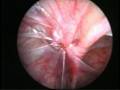

The commonly misleading history given by the parents is that the child may have had a trivial trauma or an insect bite. However, for the clinician the golden rule should be ‘Any acute scrotum is testicular torsion unless proved otherwise’. Investigations like ultrasound and color doppler may be done to help in the diagnosis. However, in the event of any doubt, it is safest to do a surgical exploration of the scrotum. The other uncommon causes of acute scrotum are acute epidydymo orchitis, scrotal abscess, idiopathic scrotal oedema and torsion of appendix of the testis. ●

Torsion of Left Undescended Testis (Pre operative and Operative Photo)

Torsion Testis (Pre and Per operative photo)